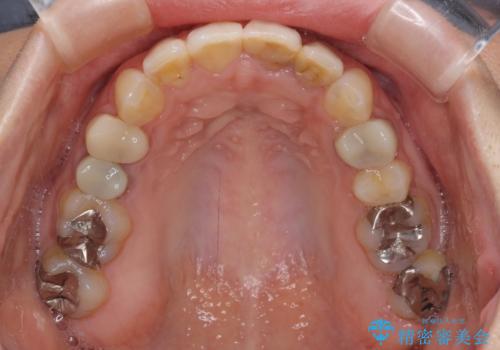

【モニター】前歯のデコボコと奥歯の虫歯 インビザライン治療と奥歯のセラミック治療

- 前歯のデコボコと奥歯の虫歯を気にして来院された患者様です。

主に下顎歯列全体の後方移動とIPR(歯と歯の間を削る)によってデコボコが解消するように設計し、インビザラインにより治療を行うこととしました。

下顎前歯の叢生が速やかに改善されたため、1年3か月で治療を終えることができました。

下顎前歯は後戻りを起こしやすいため、舌側を細いワイヤーで固定することで後戻り対策を行っています。